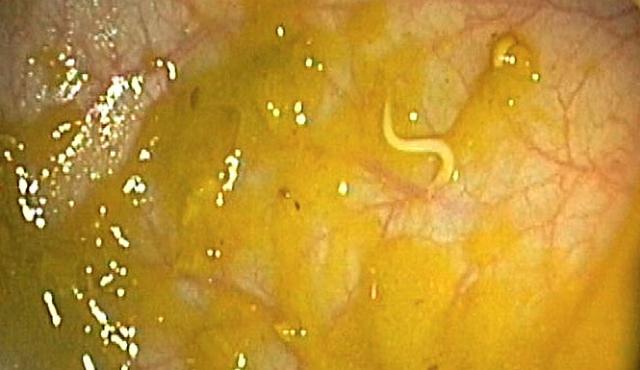

Crijeva - tisuće bakterija, virusa i crva ovdje živi. Neki imaju glave, a neki mogu poprilično izrasti.